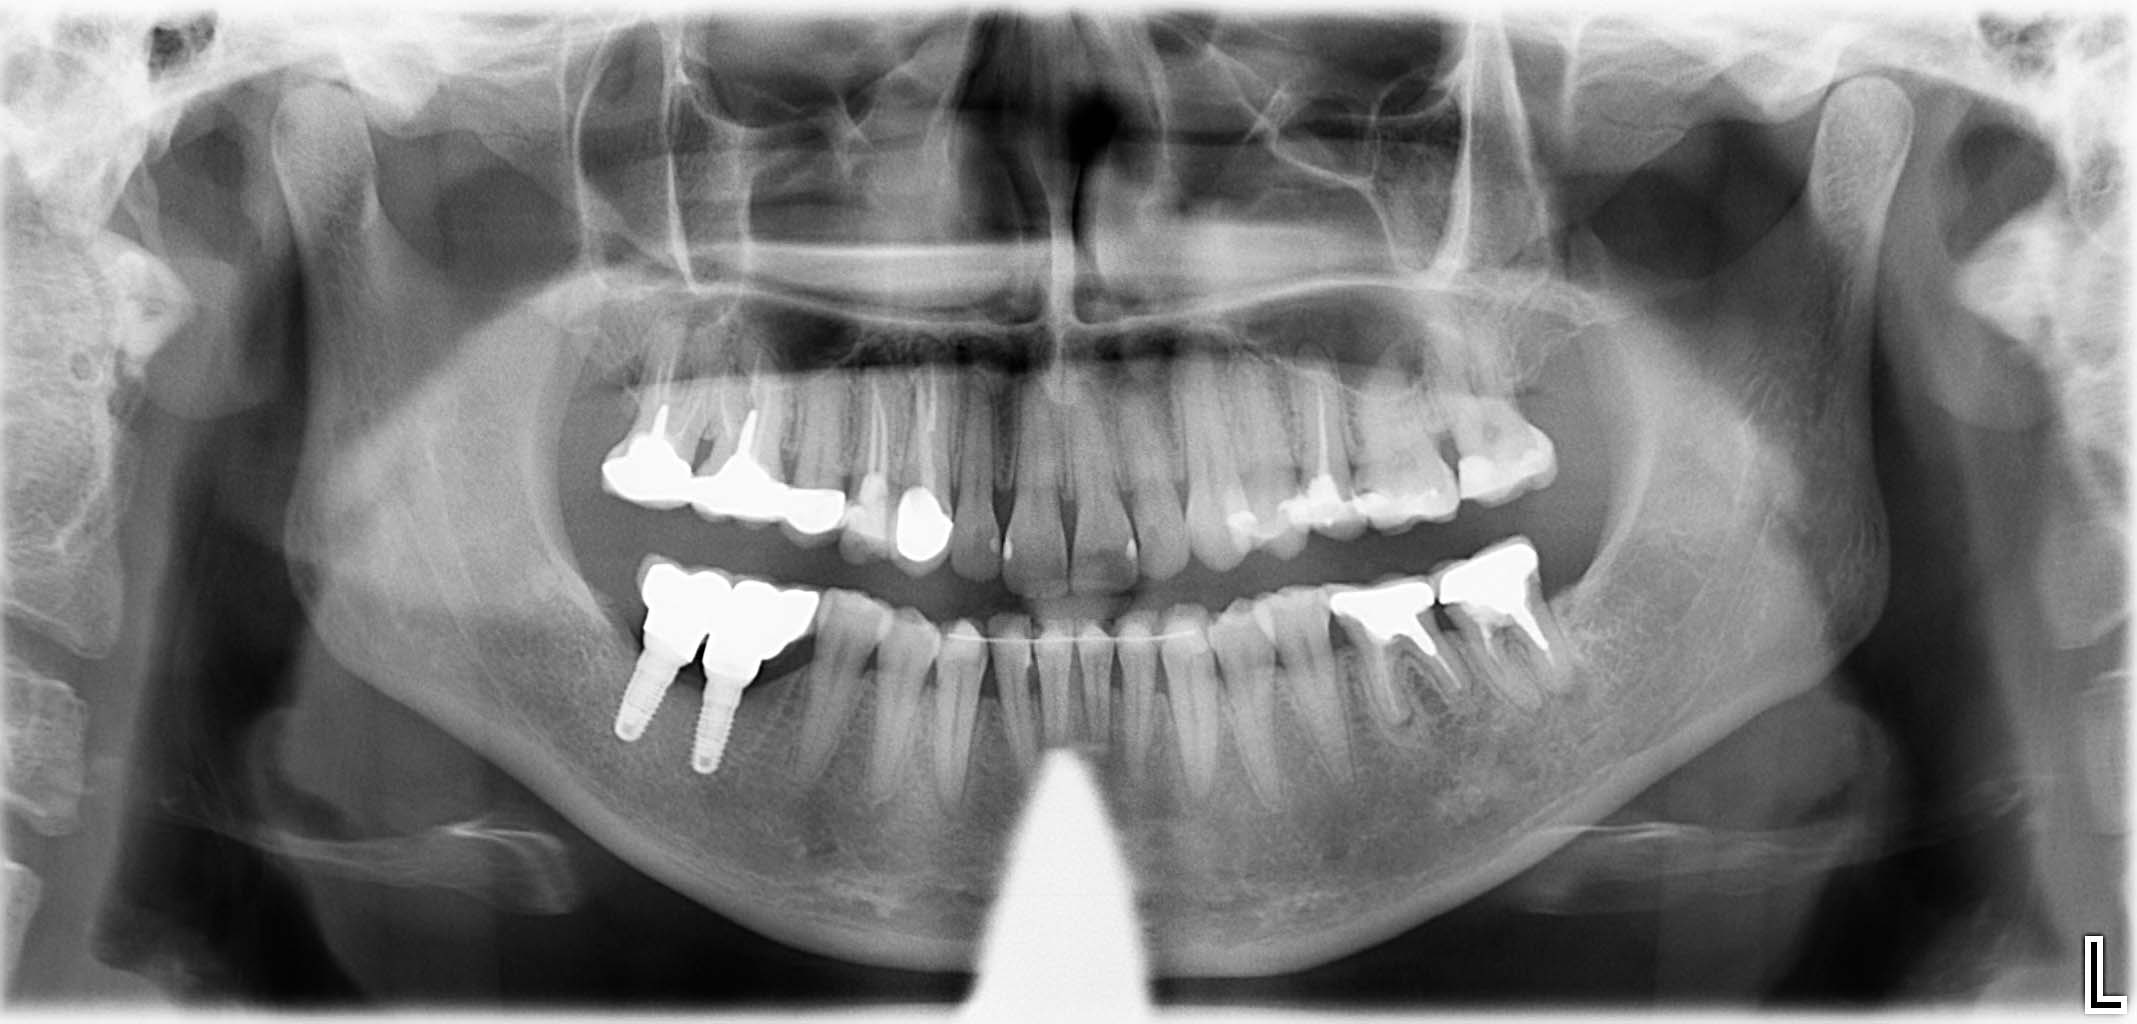

Erfolgreich implantierte Patientenfälle (klinische Fotos)